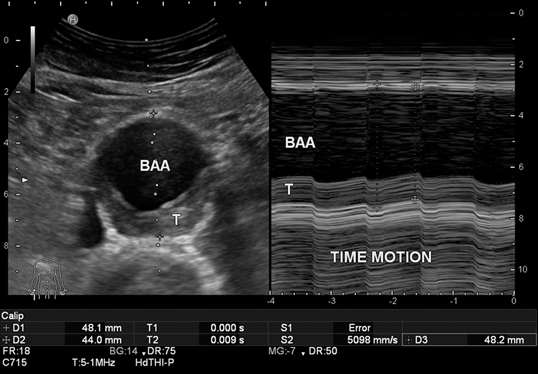

Visualization of an AAA with cardiac-cycle-dependent diameter variation in real-time B-mode (left), while diameter variation (systolic/diastolic) is documented in time-motion mode over time (in the anteroposterior plane) (right).

When determining aortic diameter accurately, it must be borne in mind that fluctuations of 2– 4 mm in systolic/diastolic diameter are possible both with a normal aorta as well as in the presence of an aortic aneurysm (Fig. 1). There are only scant ultrasound studies that address the issue of cardiac cycle-dependent measurements [7], and in statistical CT measurements it is simply not possible to take these fluctuations into consideration for method-specific reasons [4]. This explains small variations both in monitoring as well as in method comparisons. Although ECG-gated measurement would be helpful [2, 3], this cannot be required of practice-based screening programs, nor is it practicable.

Fig. 1

Diameter fluctuations from 48 mm (systolic) to 44 mm (diastolic) in time-motion modus (recording diameter change over time at the point of the sound beam visualized in B-mode). In B-mode cross section (right) with 48 mm diameter, incidental visualization in systole. Measurements made according to the leading-edge method (see video clip). BAA abdominal aortic aneurysm, T thrombus